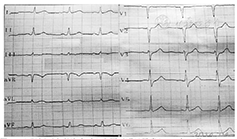

患者 男,43岁,因"反复胸前区疼痛约10 h,加重约3 h"入院。患者2014年2月5日早晨8: 00左右无明显诱因突然出现胸前区、上腹部阵发性疼痛,疼痛位置不固定,向背部放射,伴有胸闷,症状数分钟后能自行缓解,但症状反复发作,当日13: 00来我院诊治,14: 05查丙氨酸氨基转移酶(ALT) 25 U/L(正常值9~ 52 U/L)、天冬氨酸氨基转移酶(AST) 33 U/L(正常值15~ 46 U/L )、乳酸脱氢酶(LDH) 442 U/L(正常值313~ 618 U/L)、肌酸激酶(CK) 71 U/L(正常值30~ 170 U/L )、肌酸激酶同工酶(CK-MB) 20 U/L(正常值0~ 16 U/L)。患者14: 27胸痛间歇期查十二导联心电图示下侧壁导联ST段改变(图1),后患者疼痛有所好转,拟诊腹痛待查,不排除冠心病、心绞痛,给予麝香保心丸后患者离院。15: 00左右患者疼痛加重,剑突下疼痛明显,症状持续不缓解,阵发性加剧,伴有恶心、呕吐、出汗,无晕厥、心悸、呼吸困难,收入院进一步诊治。患者平素吸烟,每天约吸1包烟,否认高血压、糖尿病病史。查体:血压154/109 mmHg (1 mmHg= 0.133 kPa),两肺未闻及干、湿性啰音,心率92次/min,律齐,无杂音,腹平软,上腹部轻压痛,无反跳痛,未触及包块,肝脾肋缘下未触及,Murphy征阴性,肝肾区无叩击痛,双下肢无水肿。胸部X线片无异常。18: 25十二导联心电图无异常(图2)。18: 26查ALT 28 U/L、AST 19 U/L、LDH 433 U/L、CK 83 U/L、CK-MB 16 U/L,血糖、肾功能、血淀粉酶、凝血功能无异常。给予吸氧、严密监护、抗血小板聚集、扩张冠状动脉等处理。胸部、腹部增强CT未见胸腹部异常情况,无主动脉夹层形成。患者症状缓解不明显。22: 30查ALT 27 U/L、AST 36 U/L、LDH 431 U/L、CK 289 U/L、CK-MB 58 U/L,肌钙蛋白T 253 ng/L,血淀粉酶正常。次日0: 10十八导联心电图正常(图3, 图4)。诊断为冠心病、急性心肌梗死、心功能Killip 1级,行冠状动脉造影检查:左前降支近中段狭窄30%,对角支无狭窄;左主干无狭窄;右冠状动脉无狭窄,左回旋支近段完全闭塞;各血管间未见明显的侧支循环(图5)。手术中发现左回旋支近段严重固定狭窄并急性闭塞,予回旋支植入2枚药物支架。数天后患者病情好转出院。